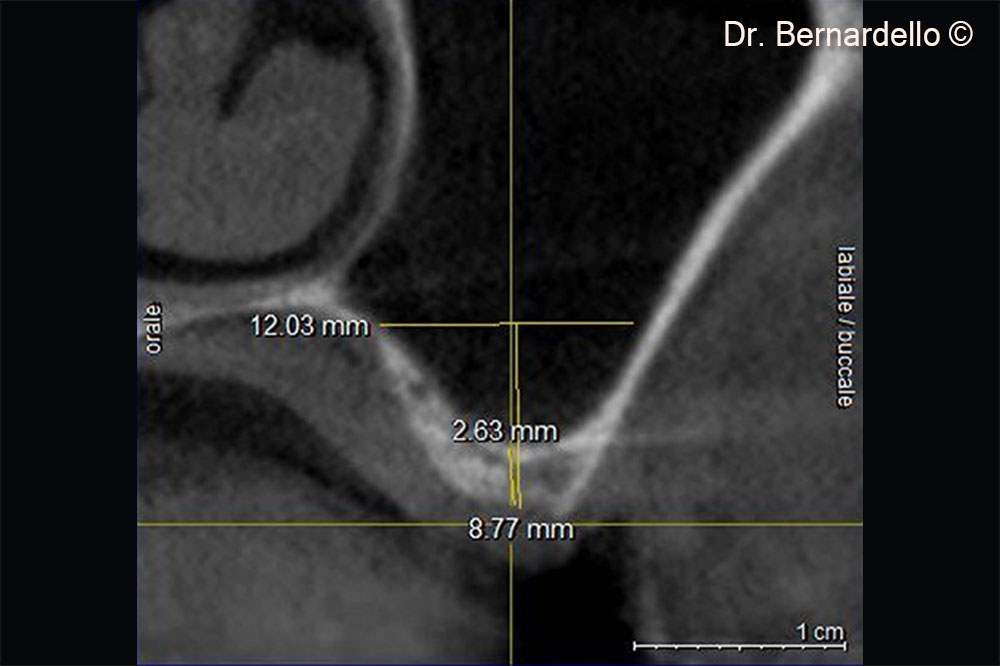

Above the apex on the implant, it is possible to see a thin layer of cortical bone